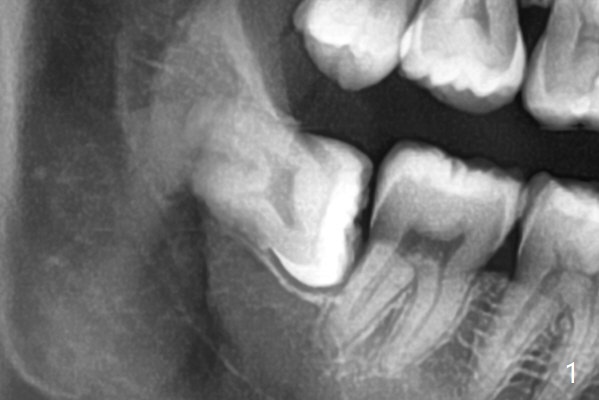

With 1/2 of Collagen plug placed in the apical portion of the socket, Bond Apatite (1 cc, A) is placed, followed by the other 1/2 of Collagen Plug coronally (Fig.2).